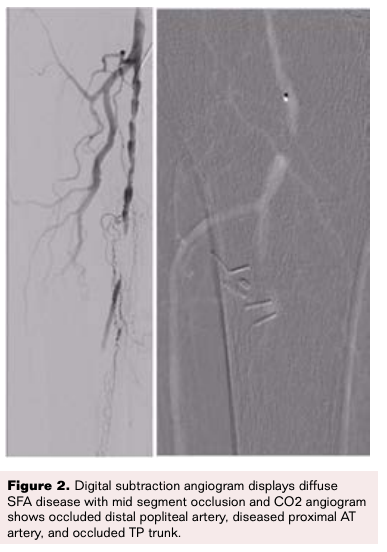

A 93-year-old woman with history of hypertension, permanent atrial fibrillation, prior cigarette smoking, chronic stage 3 kidney disease, and moderate aortic stenosis, presented to an outside hospital with disabling rest pain, discoloration and swelling of her right lower extremity. Physical examination revealed pale and cool right foot, absent dorsalis pedis and faint posterior tibial pulses, and gangrenous changes involving her second and third toes (Figure 1A). An urgent peripheral angiogram showed severely calcified, diffusely diseased superficial femoral artery (SFA) with CTO in the mid SFA segment, a second CTO in the distal popliteal artery, an occluded peroneal artery, densely calcified and diffusely diseased anterior tibial artery, and a patent but calcified posterior tibial artery with minimal antegrade flow.

The patient was evaluated and a shared decision was made to proceed with a repeat intervention attempt to revascularize her leg in an attempt to prevent amputation and relieve her symptoms. She was promptly taken to the catheterization laboratory. Antegrade access was obtained under ultrasound guidance using a micropuncture access set (Cook Medical), and up-sized for a 6Fr x 10 cm Pinnacle sheath (Terumo Interventional Systems). Therapeutic anticoagulation was administered and activated clotting time (ACT) was maintained at more than 200 seconds. Digital subtraction angiography of the right lower extremity with runoff was obtained (Figure 2).